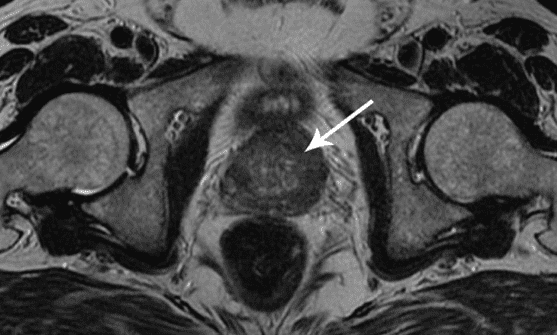

Rak prostate kod muškarca starog 58 godina. Uzrok - dugotrajna apstinencija (od 51 godine). Pacijent je umro.